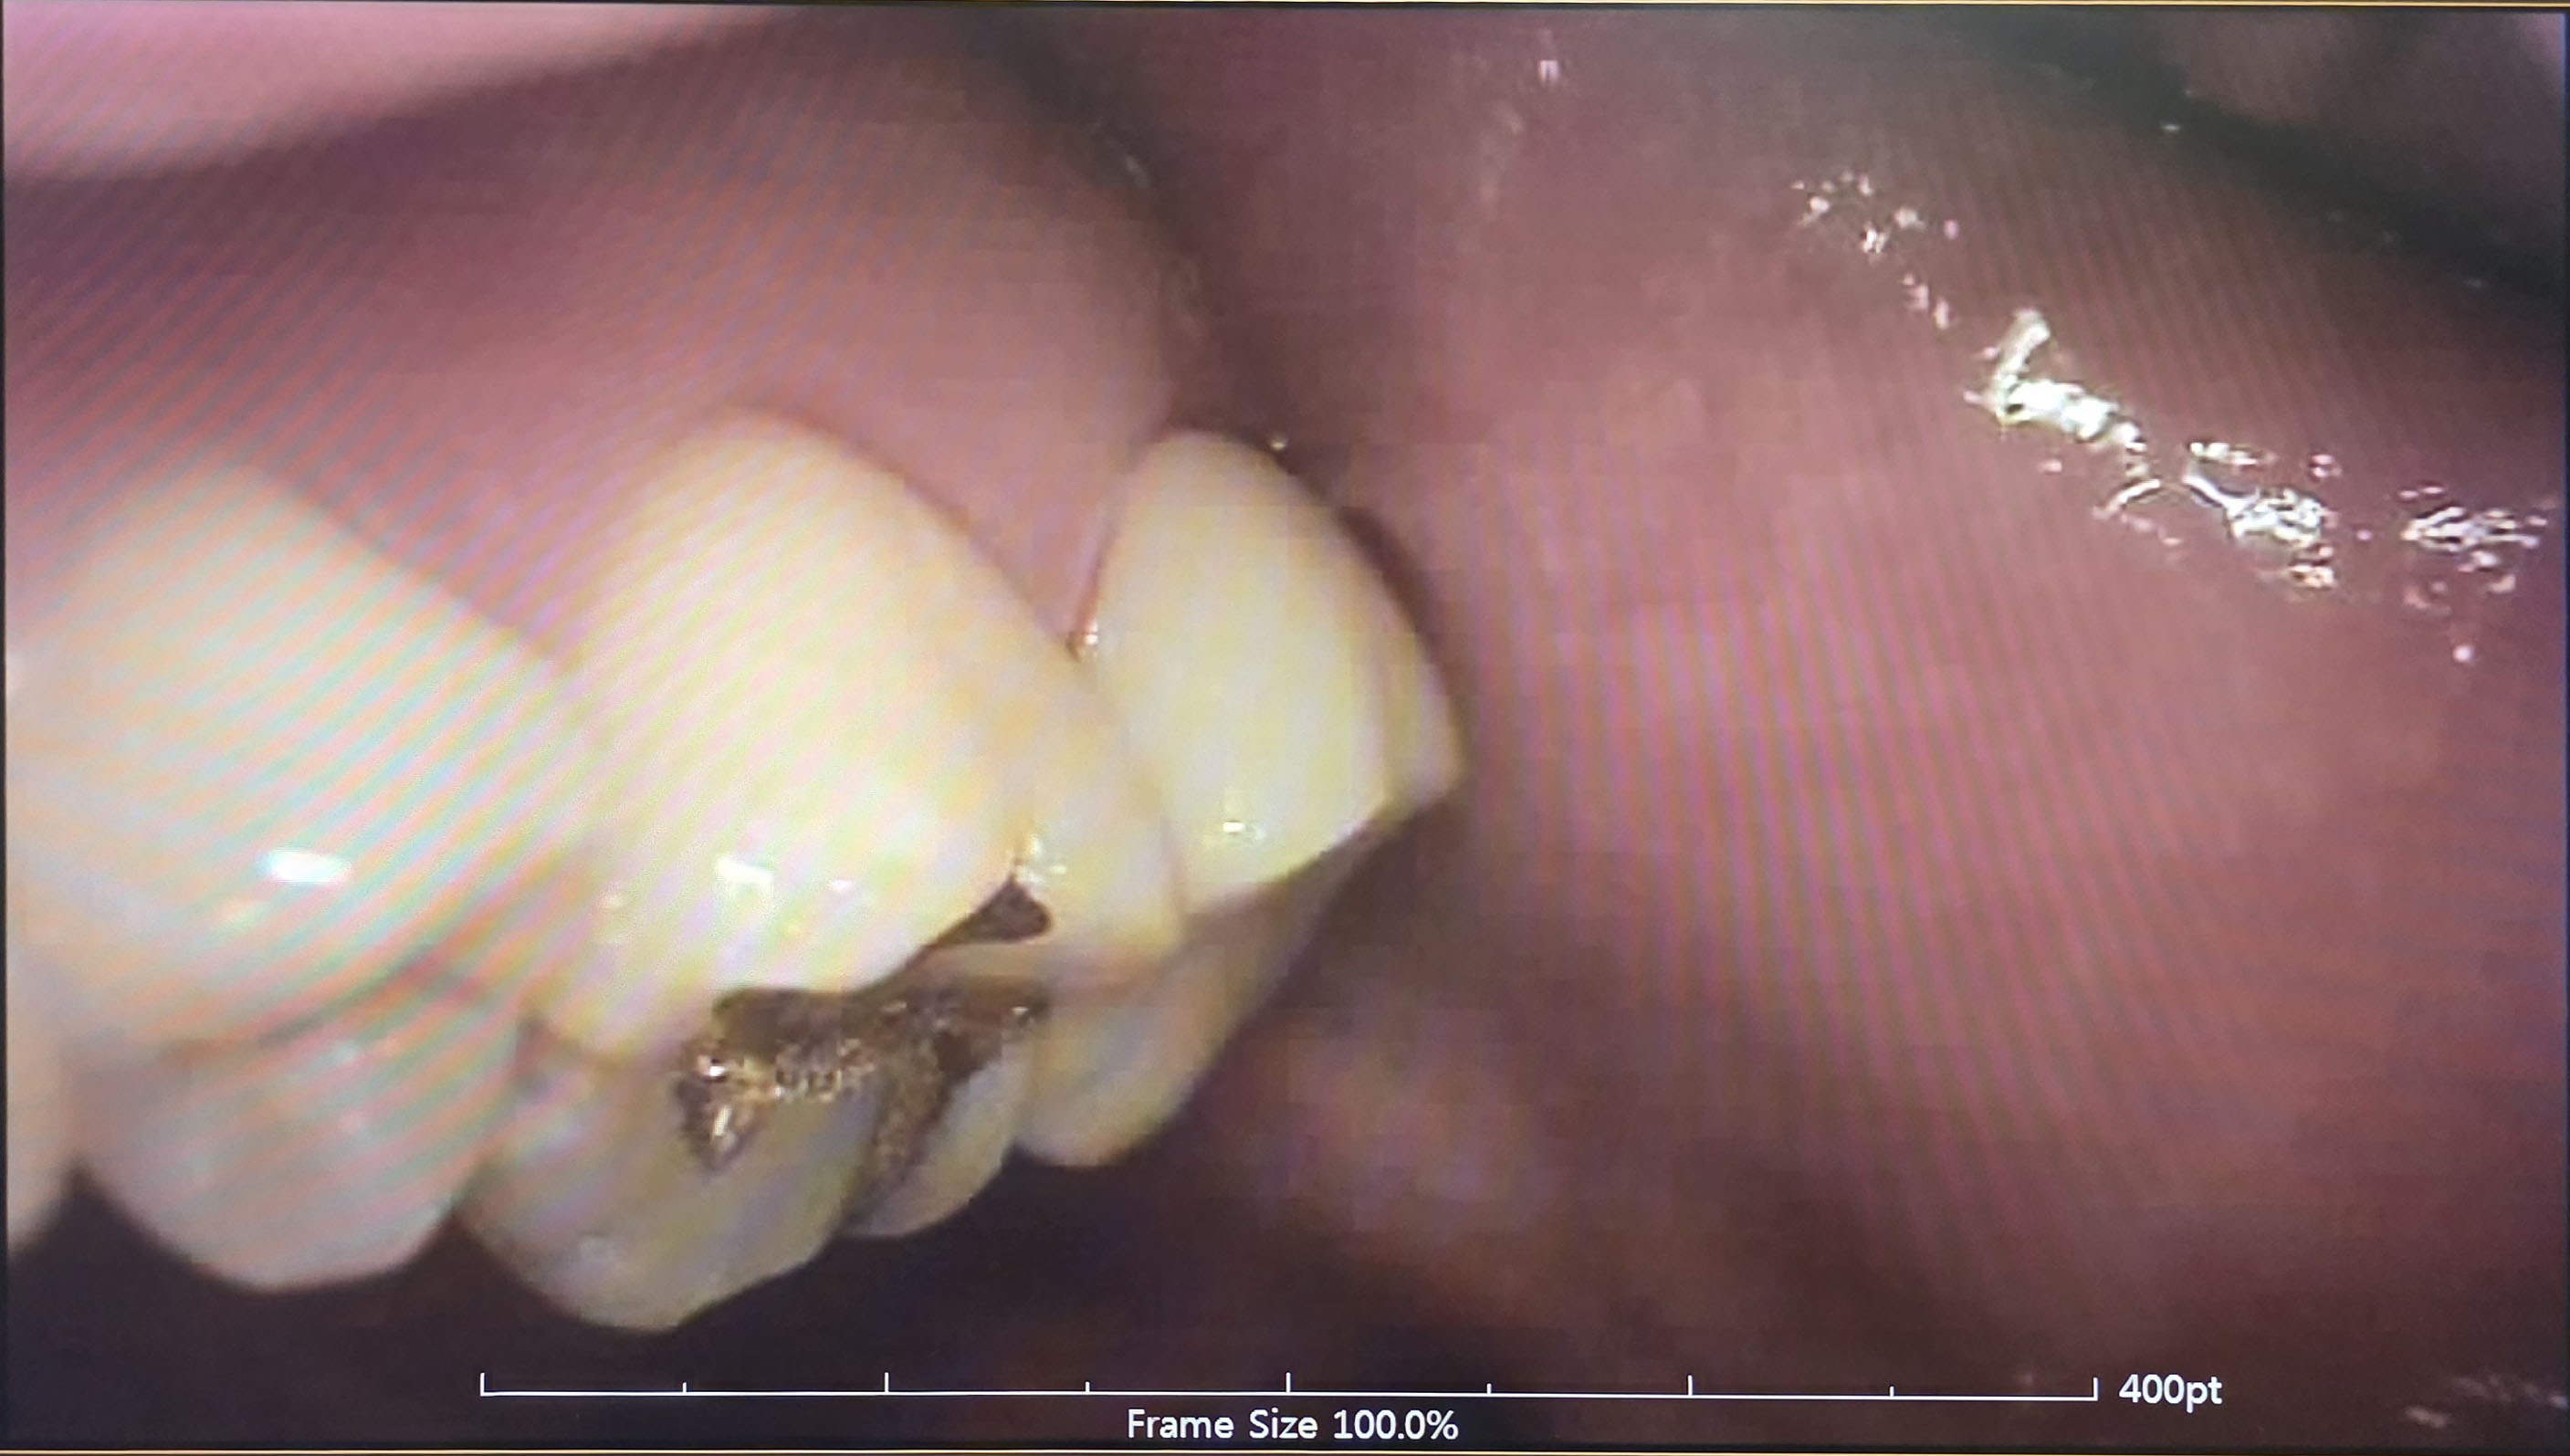

크라운 치료 완료!!

그 누렇던 치아가 자리를 잡고 나니 감쪽같네요! ㅎㅎ;;

아주 잘 완성된 듯합니다.